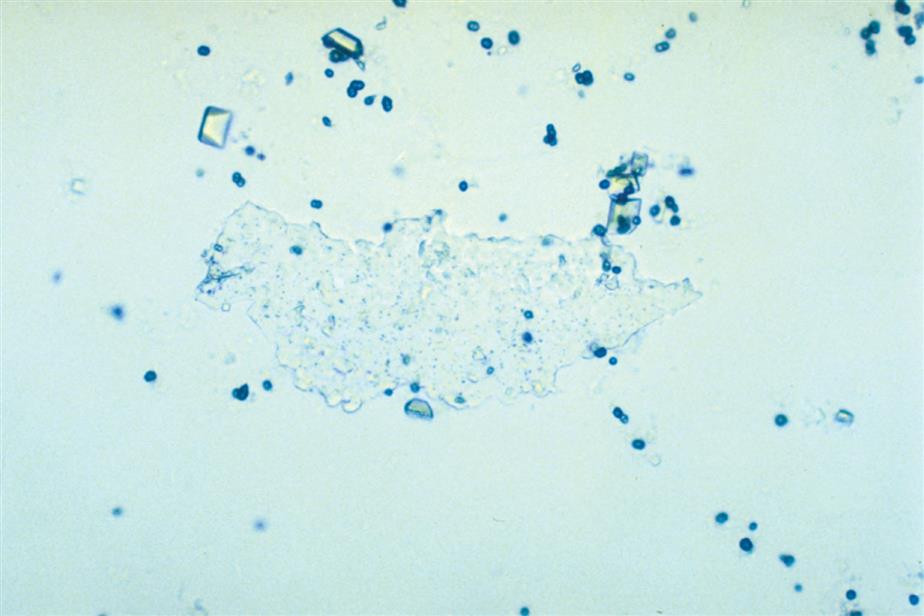

Calcium phosphate is present in urine as dibasic calcium phosphate (i.e., CaHPO4, calcium monohydrogen phosphate) and as monobasic calcium phosphate (i.e., Ca[H2PO4]2, calcium biphosphate). These similar yet different compounds precipitate out of solution in distinctly different crystalline shapes. Dibasic calcium phosphate crystals, sometimes called stellar phosphates, appear as colorless, slat-like prisms arranged in small groupings or in a rosette pattern (Fig. 7.95). Each prism has one tapered or pointed end, with the other end squared off. Another, less common, form of dibasic calcium phosphate crystals are thin, long needles arranged in bundles or sheaves (Fig. 7.96). In contrast, monobasic calcium phosphate crystals usually appear microscopically as irregular granular sheets (Fig. 7.97) or flat plates that can be large and may even be noticed floating on the top of a urine specimen. These colorless crystalline sheets can resemble large degenerating squamous epithelial cells.